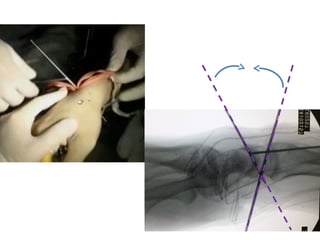

This presentation discusses various topics related to the wrist including static scapholunate ligament dissociation, dorsal ganglion cysts originating from the dorsal capsulolunate septum, treatment of scaphoid pseudarthrosis using a bone graft from the distal radius placed under the extensor tendons, and proximal pole scaphoid pseudarthrosis treated with capitolunate arthrodesis. It also thanks attendees and provides instructions for accessing the presentation online.